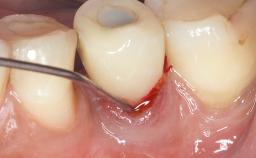

Open-Flap Debridement for the Management of Peri-Implant Mucositis Associated with Excess Cement

A 79-year-old female patient was referred to the Department of Periodontology of the University of Bern, Switzerland by her private dentist in May 2019. She had been rehabilitated in May 2005 with two tissue-level implants (Institut Straumann AG, Basel Switzerland) at sites 13 and 15, supporting a three-unit cemented fixed dental prosthesis (FDP). The metal-ceramic FDP had been cemented permanently with a glass-ionomer cement (Ketac Cem; 3M ESPE, Seefeld, Germany). Implant 13 had been diagnosed with peri-implant mucositis by the referring dentist in the course of regular supportive therapy. The patient was in good general health, did not smoke, and exhibited good self-performed plaque control.